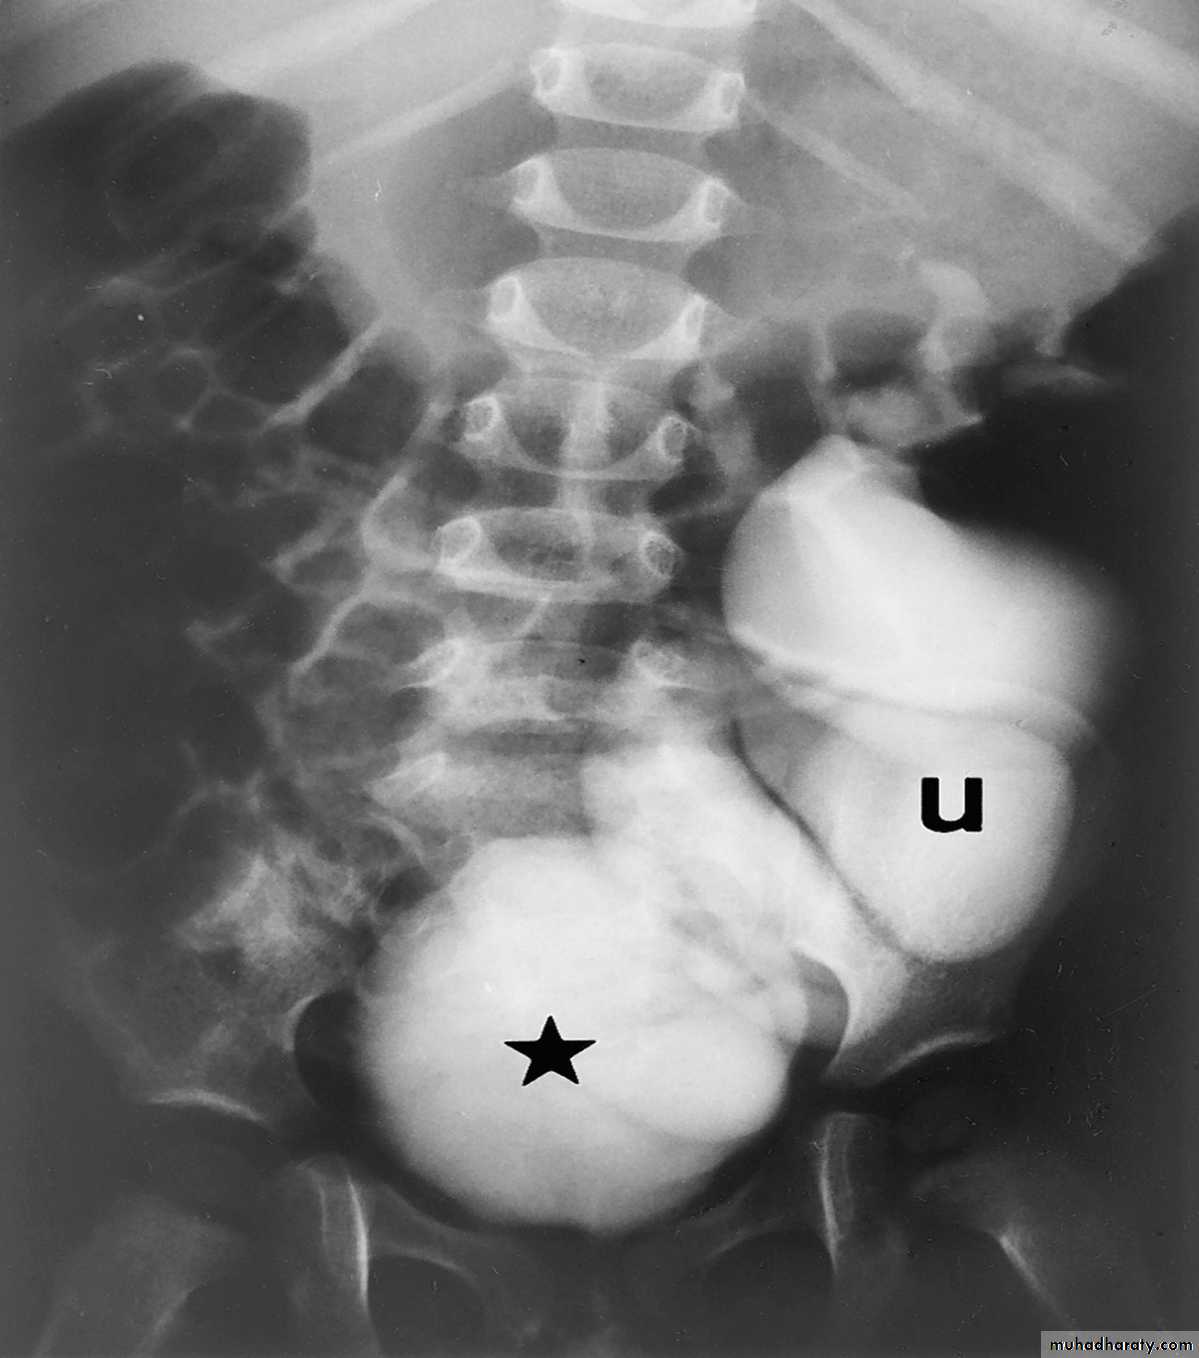

18- PUJ obstruction

20- PUJ obstruction